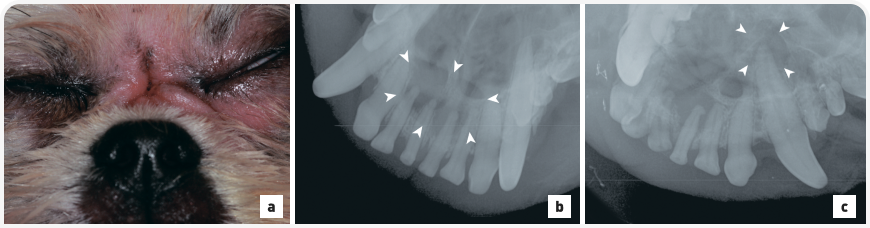

Рисунок 1. (a) Тяжелая степень отложения зубного камня на левых премолярах верхней челюсти у чихуахуа. Обратите внимание, что пациент располагается в дорсальном лежачем положении для осмотра ротовой полости под общей анестезией. (b) Внутриротовая рентгенограмма зубов (левая латеральная проекция клыка, техника деления угла пополам) показывает верхние левые третий резец, клык и премоляры с первого по третий. Наблюдается легкий пародонтит, показания к удалению отсутствуют. Обратите внимание на значительное отложение зубного камня на коронке левого третьего премоляра верхней челюсти (стрелка).

Количество сформировавшегося зубного налета, а также зубного камня не всегда коррелирует со степенью тяжести пародонтита. У некоторых собак мелких пород при осмотре полости рта выявляется значительное отложение зубного камня, но при этом по результатам рентгенографии диагностируется легкая форма пародонтита (Рис. 1). У других собак стадия заболевания оказывается гораздо серьезнее, чем можно было бы предположить по количеству зубного камня (Рис. 2). Оценка степени тяжести пародонтита при осмотре полости рта у собаки является важным компонентом общего физикального осмотра. Однако чтобы определить истинный масштаб поражения и, соответственно, назначить необходимое лечение заболевания, необходимо тщательное обследование пациента под общей анестезией, включая измерение глубины зубодесневых карманов, рентгенографию зубов.

Рисунок 2. (a) Легкое отложение налета и зубного камня на правых премолярах нижней челюсти у той-пуделя в возрасте 2 лет. Обратите внимание, что пациент располагается в дорсальном лежачем положении для осмотра ротовой полости под общей анестезией. В области фуркации правого четвертого премоляра нижней челюсти видна легкая рецессия десны с накоплением зубного налета (стрелка). Владелец чистил зубы этой собаке два раза в день. (b) Внутриротовая рентгенография зубов (визуализация правых премоляров, техника деления угла пополам) демонстрирует тяжелый пародонтит, характеризующийся обнажением фуркации третьего и четвертого премоляров (стрелки). Данные зубы были удалены без осложнений, наряду с несколькими другими зубами вследствие тяжелого пародонтита.